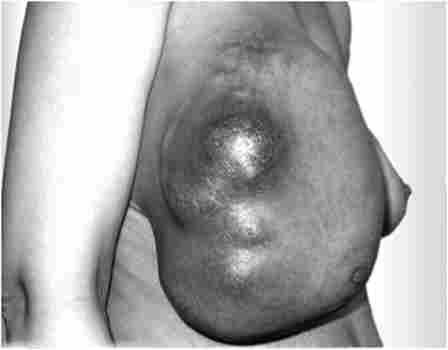

дифузні форми (рис. 8.1) відносяться до рідкісних форм РМЗ і характеризуються швидким розвитком процесу як в самому органі, так і в навколишньому тканини; раннім і великим лімфогенним і гематогенним метастазуванням. Вони швидко рецидивують після радикального лікування.

Дифузна форма раку молочної залози

Мал. 8.1. Дифузна форма раку молочної залози